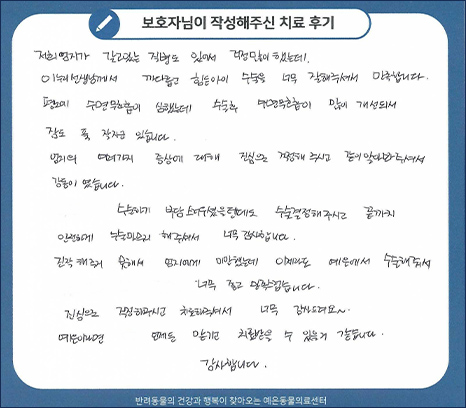

치료 후기 02

저희 엄지가 갖고있는 질병도 있어서 걱정 많이 했는데 이누리 선생님께서 까다롭고 힘든 아이 수술을

너무 잘해주셔서 만족합니다. 평소에 수면 무호흡이 심했는데 수술 후 수면무호흡이 많이 개선돼서

잠도 푹 잘자고 있습니다. 엄지의 여러가지 증상에 대해 진심으로 걱정해 주시고 같이 알아봐 주셔서

감동이였습니다. 수술하기 부담스러우셨을텐데도 수술 결정해주시고 끝까지 안전하게

수술을 마무리 해주셔서 너무 감사합니다. 진작 해주지 못해서 엄지에게 미안했는데 이제라도 예은에서

수술해줘서 너무 좋고 만족스럽습니다. 진심으로 걱정해주시고 치료해주셔서 너무 감사드려요.

예은이라면 언제든 맡기고 치료받을 수 있을 것 같습니다. 감사합니다.